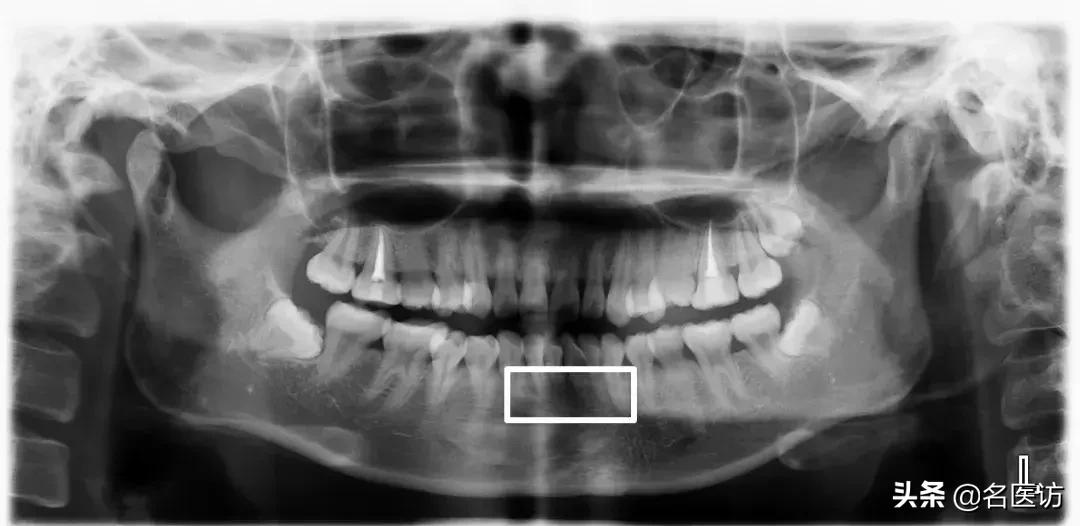

埋伏牙

多生牙

阻生牙